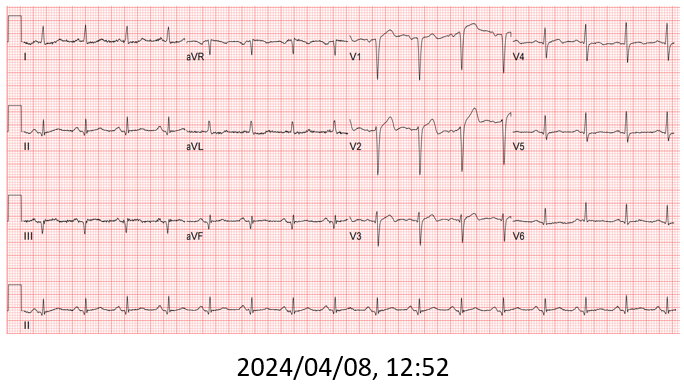

A 57-year-old man with underlying hypertension and hyperuricemia presented to our emergency department with intermittent chest pain for 3 days. Cardiac enzymes were elevated (hs-Troponin I: 2749.1 ng/L, creatine kinase: 207 U/L, CK-MB: 13.0 ng/mL) and he was diagnosed with non-ST elevation myocardial infarction.

The patient received primary percutaneous coronary intervention (PCI) with balloon angioplasty (POBA) and a drug-eluted stent (DES) for middle LAD. Three days later he underwent staged PCI for RCA. After wire externalization via rendezvous technique, the patient developed acute angina, diaphoresis, and hypotension. Angiogram found a de-novo LAD lesion just distal to the stent.

During the staged PCI, antegrade approach with escalating guidewires ended up in subintimal space; retrograde approach from the first LAD-septal branch failed because there was difficulty crossing the existing mid-LAD stent. Further attempts from the third septal branch successfully reached the distal cap of the CTO via proximal descending artery, finally entering the antegrade guide extension catheter by rendezvous technique. After wire externalization and POBA for RCA, the patient became agitated from acute angina, diaphoresis and hypotension. Angiogram of LAD found an acute de novo LAD lesion adjacent to the distal stent edge, leaving only TIMI-1 flow. We stopped the RCA procedure and wired LAD, performed POBA at the de novo LAD lesion and restored coronary blood flow. Then we continued PCI of RCA with POBA followed by the deployment of two DES. Final angiogram showed adequate stent expansion and TIMI-3 flow in RCA. The patient was discharged with no further complications. Follow-up echocardiogram three months later showed improved wall motion and ejection fraction, indicating good myocardial recovery.